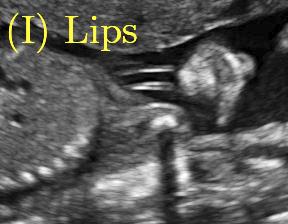

Fig. 6 compares the shadow confidence maps of the state-of-the-art methods and the proposed methods. RW and have the same parameters as used for Table I. The shadow confidence maps of the baseline, the proposed method and the proposedAG method are generated directly from input shadow images by confidence estimation networks. Overall, the proposed method and the proposedAG method achieve more visually reasonable shadow confidence estimation than the baseline and the state-of-the-art on different anatomical structures shown in Fig. 6. The proposed method and the proposedAG method are able to highlight multiple shadow regions while the RW algorithm shows limitations for most cases, especially for disjoint shadow regions.

Row I in Fig. 6 shows a fetal brain image from . The confidence estimation of shadow regions from the baseline, the proposed method and the proposedAG method are similarly accurate since we use fetal brain images to train the confidence estimation networks in these three methods. These outperform [16] and [22]. Rows (II-IV) in Fig. 6 show shadow confidence maps of non-brain anatomy from , including lips, abdominal and cardiac. The baseline failed on unseen data during inference. However, the proposed methods are able to generate accurate shadow confidence maps because of the generalized shadow features obtained by the shadow-seg module. Furthermore, the “Lips” example shows that our method is capable of detecting weaker shadow regions that have not been annotated in manual segmentation. This indicates that the confidence estimation network has learned general properties of shadow regions.